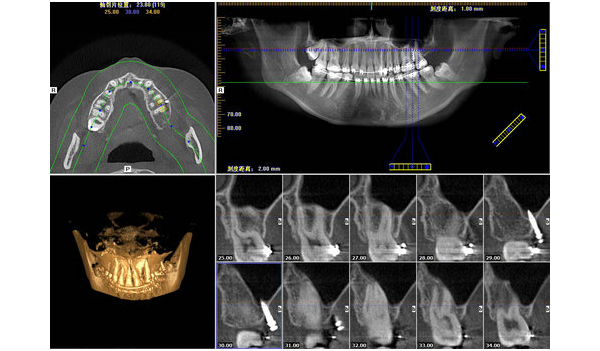

CBCT在口腔各科的應(yīng)用進(jìn)展

錐形束CT (Cone beam computer tomography,CBCT)是近年來應(yīng)用于口腔醫(yī)學(xué)領(lǐng)域的新型影像設(shè)備,其具有掃描速度快,輻射劑量低,圖像分辨率高,數(shù)據(jù)采集時(shí)間短,價(jià)格低廉等優(yōu)點(diǎn),這些優(yōu)點(diǎn)使其在口腔臨床中應(yīng)用的越來越廣泛,是目前_有前途和實(shí)用性的口腔影像設(shè)備。

口腔種植科是_先應(yīng)用CBCT并且是應(yīng)用_多的口腔臨床科室之一。CBCT能為口腔種植提供精確的三維影像,可以很好的顯示頜骨的骨質(zhì)、骨量及下頜神經(jīng)管、上頜竇等組織結(jié)構(gòu)。當(dāng)前CBCT結(jié)合第三方軟件Simplant進(jìn)行種植手術(shù),CBCT掃描后數(shù)據(jù)輸入Simplant后進(jìn)行模擬種植,建立可視化三維模型,并在其上設(shè)計(jì)_佳手術(shù)方案,制作種植手術(shù)導(dǎo)板,將種植體的理想位置轉(zhuǎn)移至患者頜骨內(nèi),大大降低了種植手術(shù)風(fēng)險(xiǎn)。

隨著CBCT的發(fā)展和在臨床上的應(yīng)用,為牙體牙髓疾病的診斷和治療提供越來越多的幫助。CBCT能清晰、立體的在頰舌向、水平位和軸位上顯示上下頜牙齒根管數(shù)目,根管的走形。如在臨床中,牙體牙髓科醫(yī)生首選根尖X線片,但對(duì)于根管結(jié)構(gòu)復(fù)雜,如上頜磨牙的近中頰側(cè)根第二根管,根尖片正常角度投照,二維影像疊加,第二根管影像難以顯示,這就需CBCT掃描重建獲得軸位、頰舌向影像,以清晰顯示根管數(shù)目、走形以及根管口的位置,為根管治療提供有力幫助。另外CBCT對(duì)于牙齒骨折尤其是牙根縱裂有較高的診斷準(zhǔn)確率,牙根縱裂通常是面向頰舌向的,如果X射線束沒有沿縱裂線直接通過,則根尖片沒有明顯表

現(xiàn),而CBCT能準(zhǔn)確的發(fā)現(xiàn)牙根縱裂等。